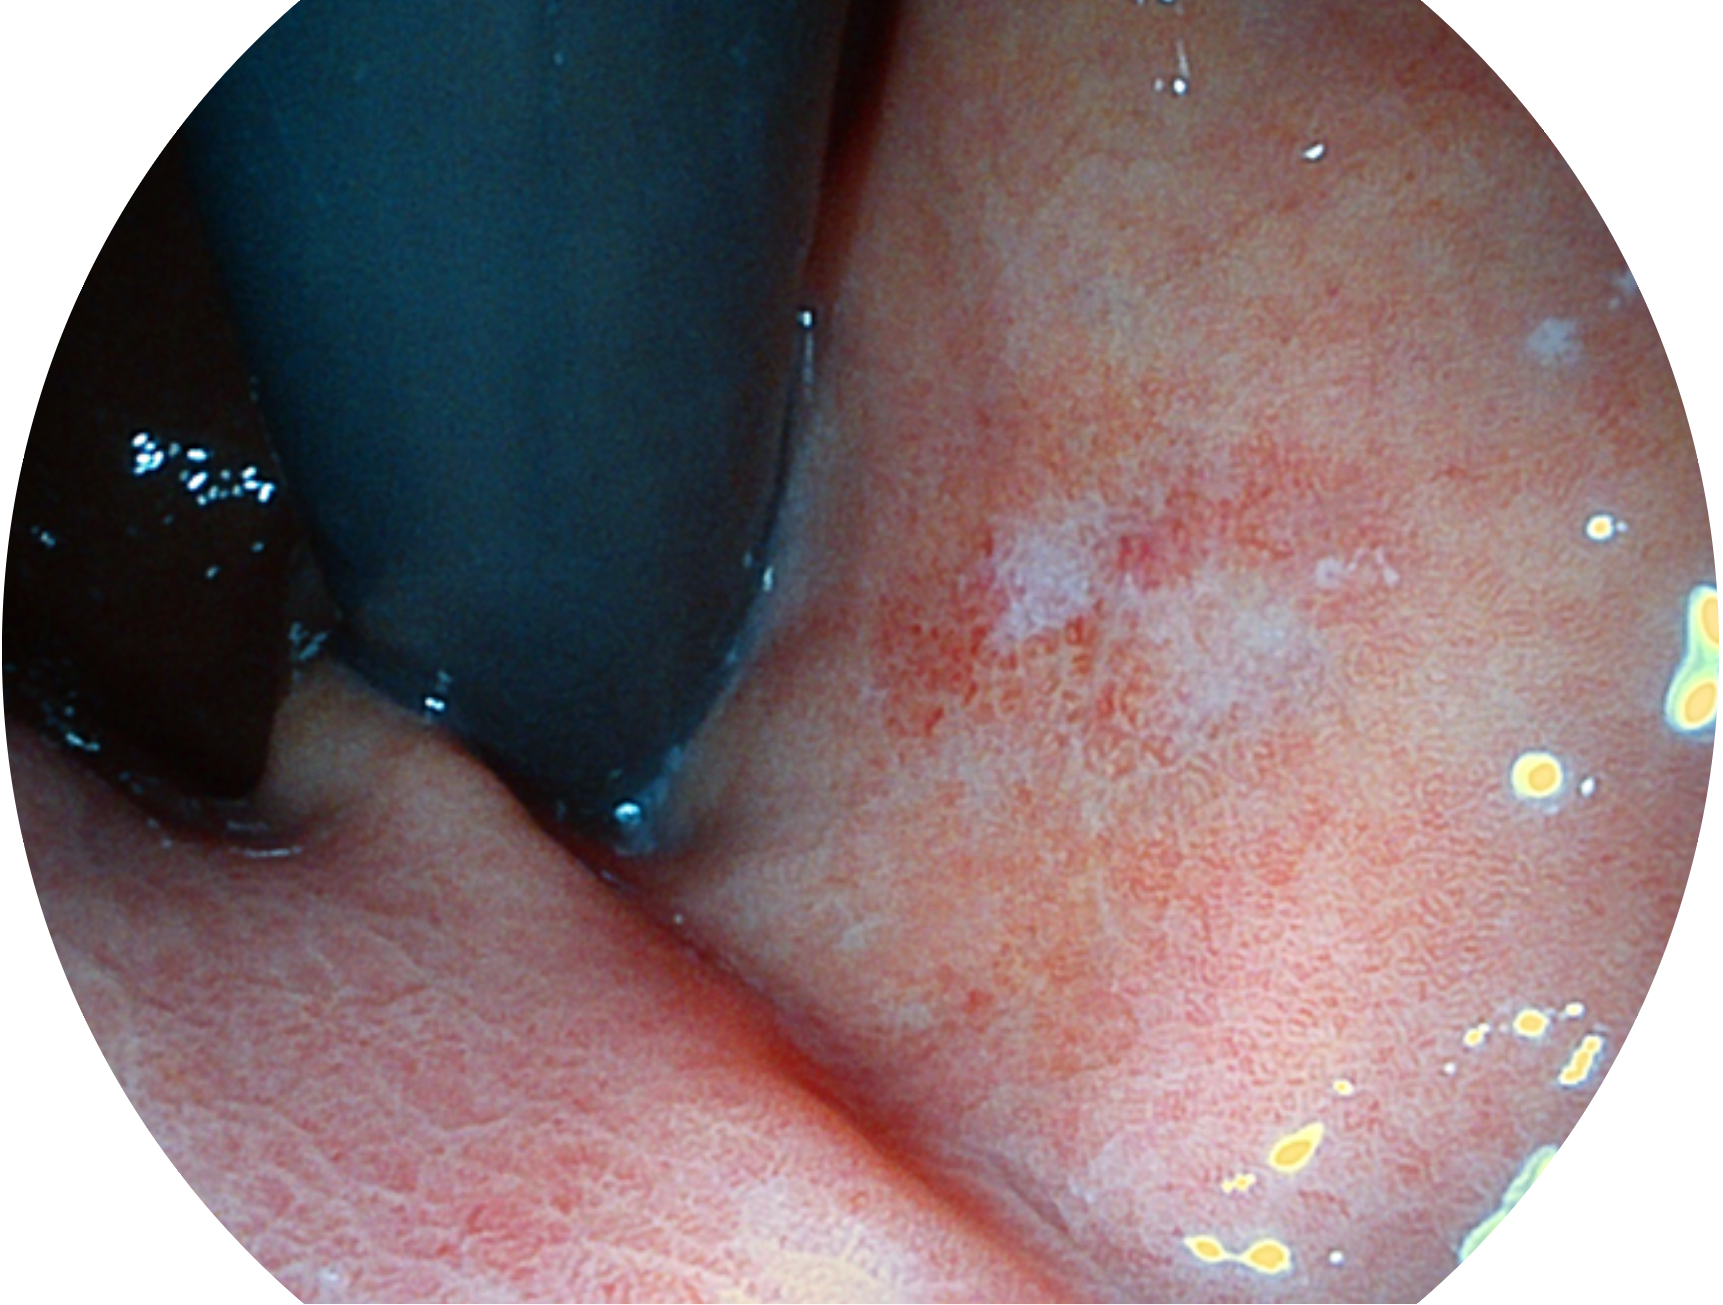

開(kāi)立新開(kāi)發(fā)的內(nèi)鏡染色技術(shù),主要是基于多波長(zhǎng)LED 光源的開(kāi)發(fā),VLS-55Q 四波長(zhǎng)LED 光源是由四個(gè)不同顏色的LED光按照相應(yīng)照明模式所規(guī)定的特定發(fā)光比例進(jìn)行合束后形成,合束后形成的照明光的光譜由紅光、綠光、藍(lán)光及藍(lán)紫光這四個(gè)不同的波段范圍構(gòu)成。具有更高光譜自由度,通過(guò)光譜比例的控制,實(shí)現(xiàn)了聚譜成像技術(shù),英文全稱為“Spectral Focused Imaging, SFI”,縮寫為“SFI”和光電復(fù)合染色成像技術(shù),英文全稱為“Versatile Intelligent Staining Technology, VIST”,縮寫為“VIST”。